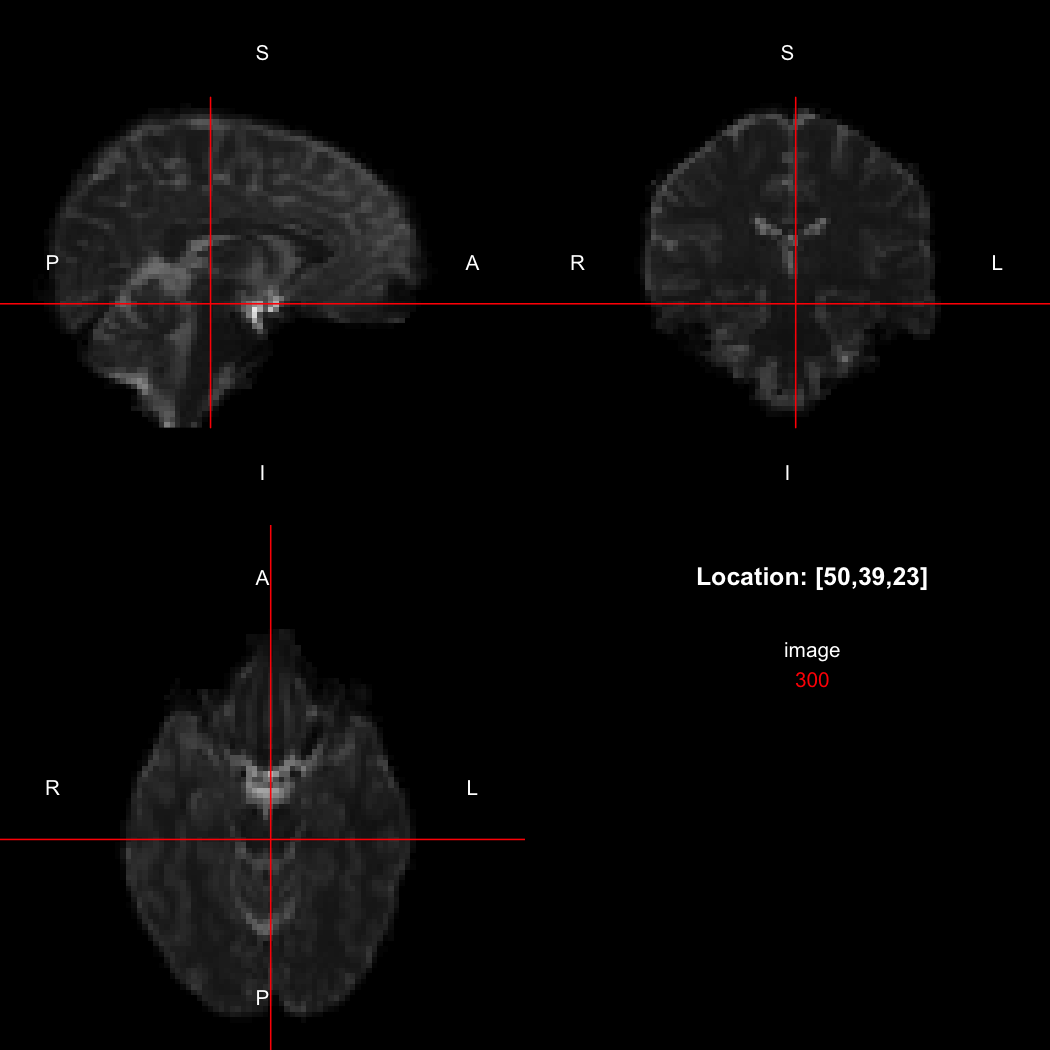

So, here, “LAS” means that the positive x-axis points left, the positive y-axis anterior and the positive z-axis superior. This is the so-called “radiological” orientation convention, and can be requested when viewing images for those who are used to it:

view(image, radiological=TRUE)

plot of chunk unnamed-chunk-12

Notice the left (L) and right (R) labels, relative to the view shown above. Setting the radiologicalView option to TRUE will make this the default for all future views.